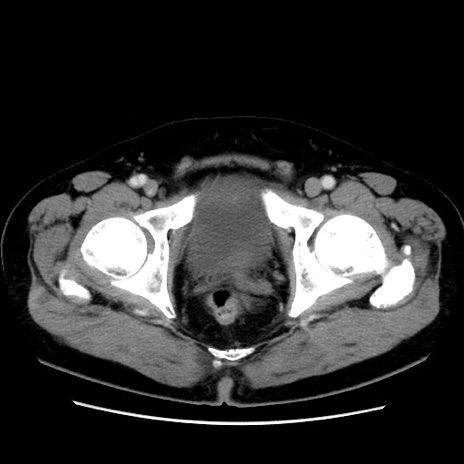

症例16(横断像)

【症例】 70歳代男性

【主訴】 腹痛、嘔吐

【現病歴】 約1ヶ月前より間欠的に腹痛と嘔吐あり、当院消化器内科を受診したところCTで多発する肝臓のLDAを指摘され、精査中であった。以降は消化器症状は安定していたが、2日前より嘔気と腹痛があり、同日より排便・排ガスが消失した。改善認めず、 本日、救急外来を受診した。

【身体所見】意識清明・会話良好、BT 36.3℃、BP 127/80mmHg、 P 80bpm、腹部:膨満あり、平坦・軟、上腹部正中および下腹部正中に圧痛あり、反跳痛なし、筋性防御なし。